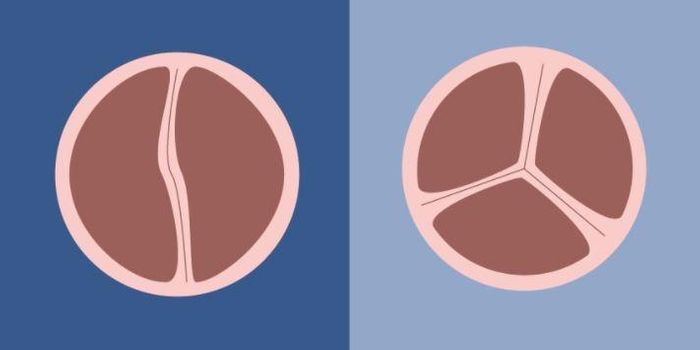

MAY 30, 2017CardiologyWhat happens during development to create the most common congenital heart defect, a bicuspid aortic valve (BAV)? The id ...